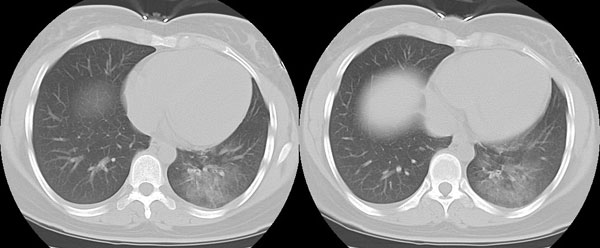

女性,25岁。反复咯血3年,再咯10天。外院x线胸片示:肺炎?支扩?

ct所见:左肺下叶基底段见大片状毛玻璃样改变,其内可见扩张细支气管。

胸部ct平扫所见:胸廓两侧欠对称,左侧略小,胸壁骨质结构完整。左肺下叶后、外基底段

见大片状毛玻璃样淡薄影,边缘渐淡,其内可见多个环形小囊状影。余肺野清晰,

肺纹理规则,气管支气管通畅,内壁光滑。心脏、大血管大小、形态、密度未见

明显异常,胸膜不厚、光滑,纵隔内未见明显肿大淋巴结。

诊断意见:左肺下叶大片状毛玻璃样淡薄影考虑支气管扩张伴出血。

对于支气管扩张的ct检查目的除了诊断有无支气管扩张外,还应该给临床提供扩张的类型,程度和范围.